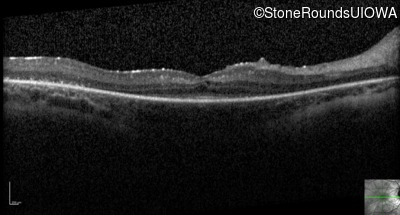

Optical Coherence Tomography - Right - 20/40 -2

Exemplar / OCT Stack